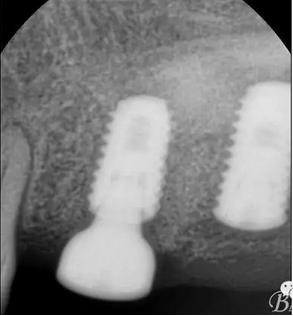

術(shù)后x光片,右上6直接上愈合基臺(tái),但未完全就位,右下7手術(shù)過(guò)程略

這是術(shù)后1月的片子,重新就位愈合基臺(tái)